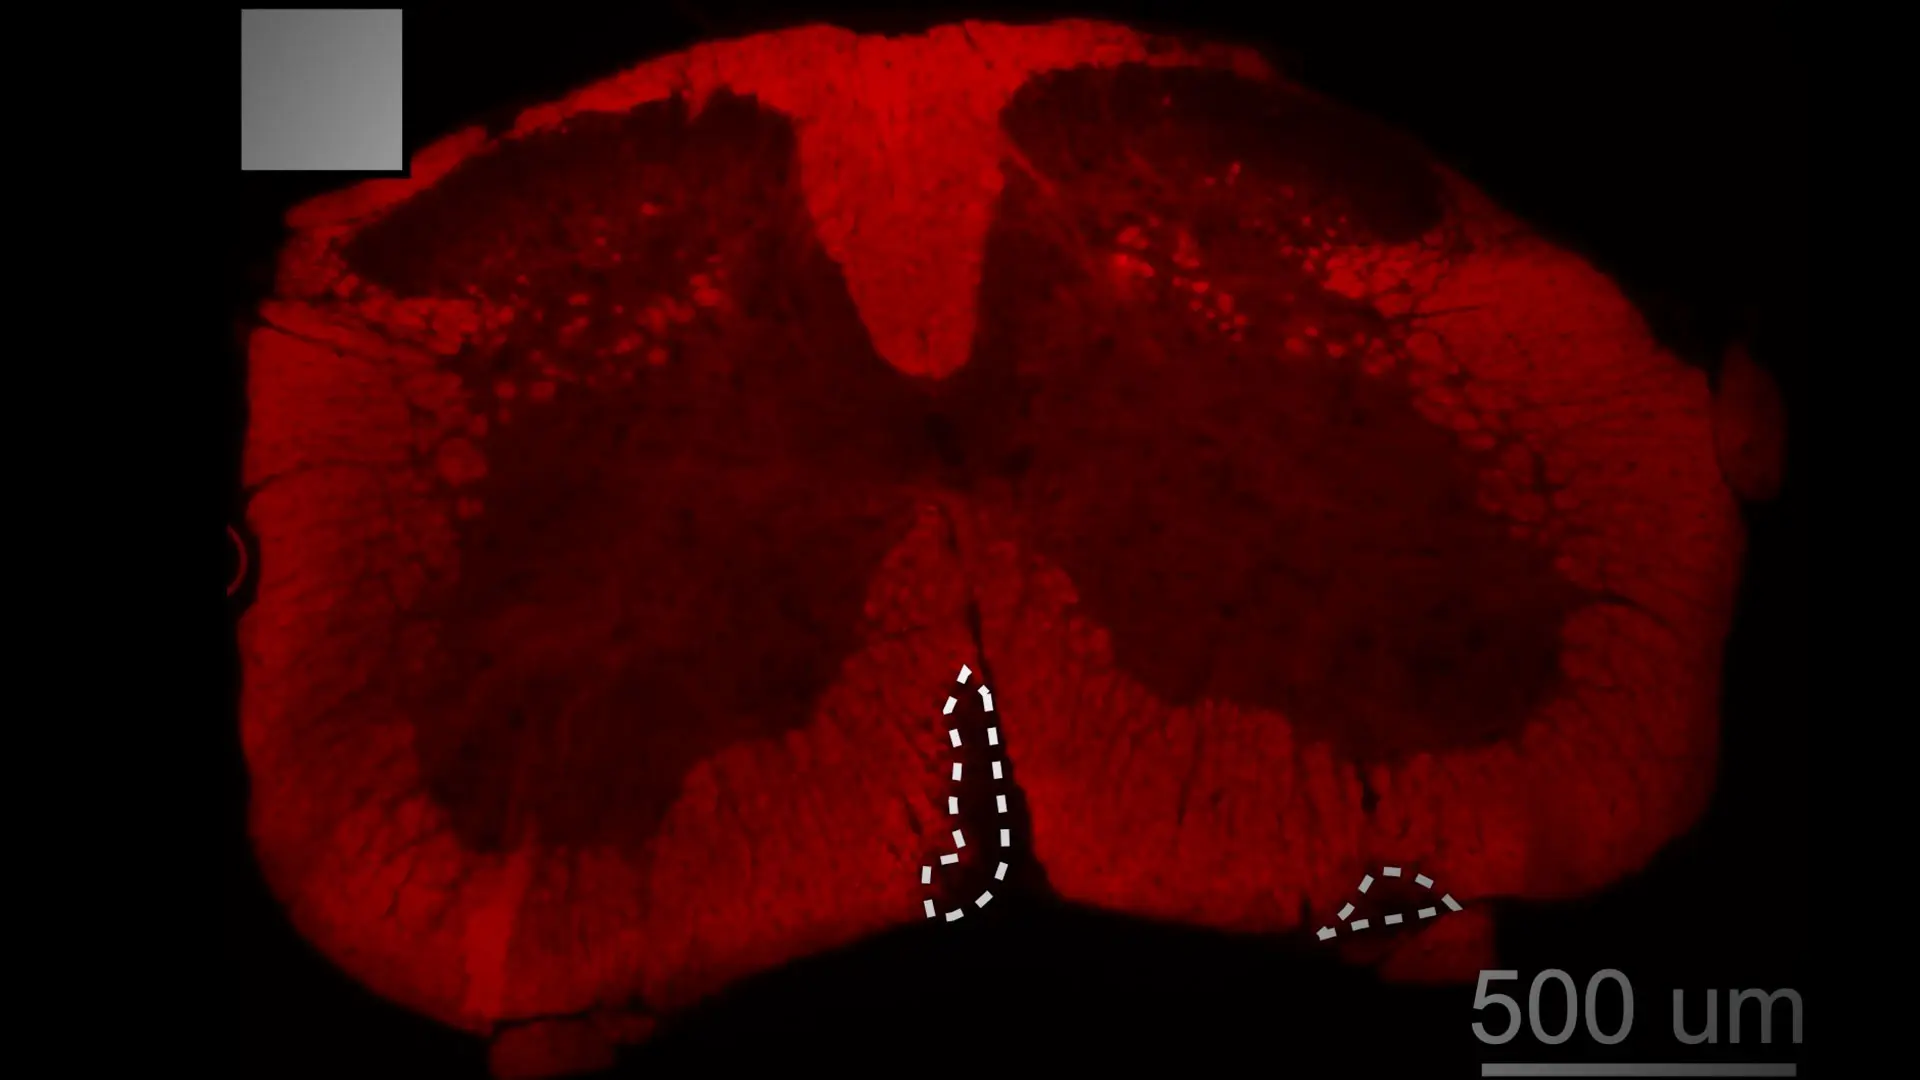

Demyelination in the spinal cord of a mouse with MS and cardiometabolic syndrome.